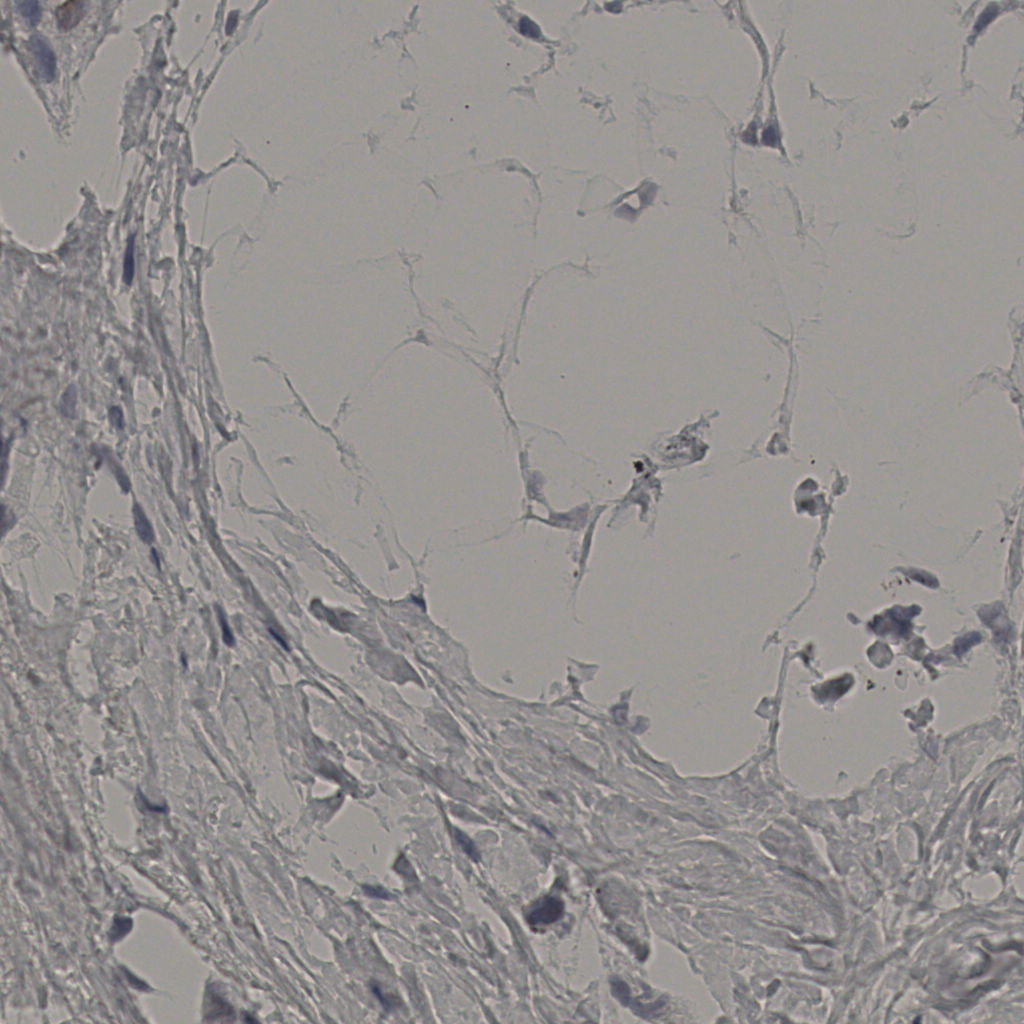

5.31%

Ki67 指数

阴 19502

阳 1093

标记后

标记前